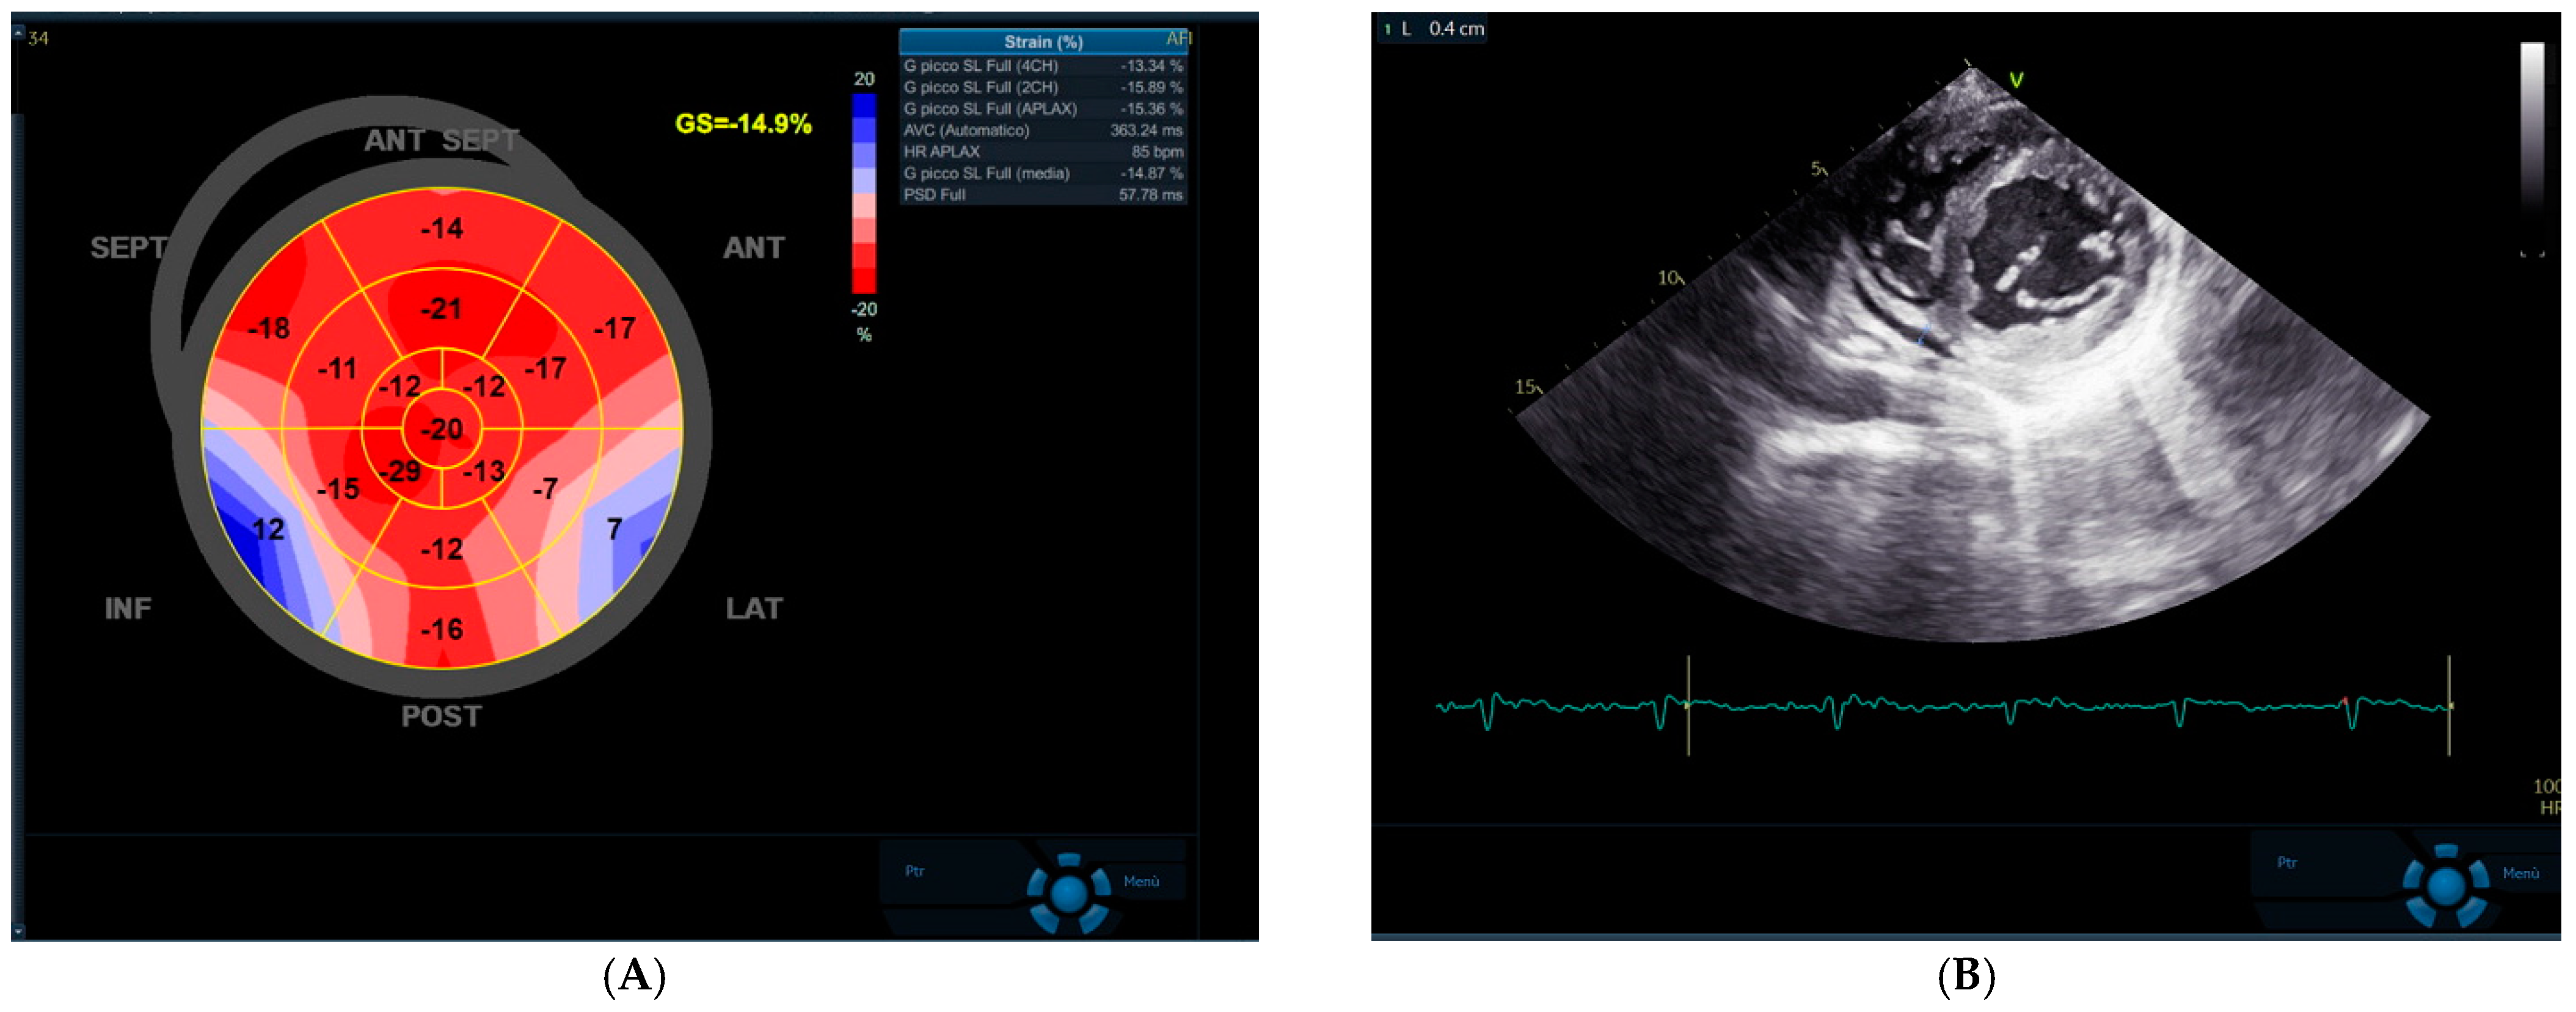

Advanced 2D echocardiogram showed normal systolic function with a mild reduction of left ventricular global longitudinal strain (GLS—14.5%, GE Healthcare Software, Little Chalfont, UK). A small circumferential pericardial effusion (<10 mm) was detected in the parasternal short-axis view (Figure 3).

Figure 3. 2D-Echocardiogram showing small reduction in left ventricular global longitudinal strain (A) and mild, circumferential pericardial effusion (B).